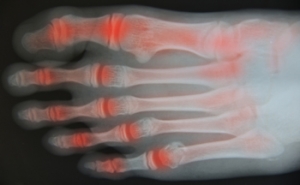

Walking May Help With Symptoms of Arthritis

Research has suggested that walking may be one of the best methods to manage the symptoms of pain, stiffness, or inflammation that can coincide with arthritis. It is important to start off slowly by building a walking routine, and with some time and experience, it should become easier when performed every day. Walking can also be beneficial for losing weight which may help lessen the stress that the joints endure. Slowly increasing the frequency, intensity, and length of time that you walk is the preferred method and can help to alleviate the aches and pain from arthritis. Many patients find that counting how many steps they take every day can help track their daily progress for maximum benefits. If you have arthritis in your feet, it is strongly suggested that you consult with a podiatrist who can offer you proper management techniques.

Research has suggested that walking may be one of the best methods to manage the symptoms of pain, stiffness, or inflammation that can coincide with arthritis. It is important to start off slowly by building a walking routine, and with some time and experience, it should become easier when performed every day. Walking can also be beneficial for losing weight which may help lessen the stress that the joints endure. Slowly increasing the frequency, intensity, and length of time that you walk is the preferred method and can help to alleviate the aches and pain from arthritis. Many patients find that counting how many steps they take every day can help track their daily progress for maximum benefits. If you have arthritis in your feet, it is strongly suggested that you consult with a podiatrist who can offer you proper management techniques.

Arthritis can be a difficult condition to live with. If you are seeking treatment, contact Ambrose Su, DPM from Cascade Foot Clinic. Our doctor can provide the care you need to keep you pain-free and on your feet.

Arthritic Foot Care

Arthritis is a term that is commonly used to describe joint pain. The condition itself can occur to anyone of any age, race, or gender, and there are over 100 types of it. Nevertheless, arthritis is more commonly found in women compared to men, and it is also more prevalent in those who are overweight. The causes of arthritis vary depending on which type of arthritis you have. Osteoarthritis for example, is often caused by injury, while rheumatoid arthritis is caused by a misdirected immune system.

Symptoms

- Swelling

- Pain

- Stiffness

- Decreased Range of Motion

Arthritic symptoms range in severity, and they may come and go. Some symptoms stay the same for several years but could potentially get worse with time. Severe cases of arthritis can prevent its sufferers from performing daily activities and make walking difficult.

Risk Factors

- Occupation – Occupations requiring repetitive knee movements have been linked to osteoarthritis

- Obesity – Excess weight can contribute to osteoarthritis development

- Infection – Microbial agents can infect the joints and trigger arthritis

- Joint Injuries – Damage to joints may lead to osteoarthritis

- Age – Risk increases with age

- Gender –Most types are more common in women

- Genetics – Arthritis can be hereditary

If you suspect your arthritis is affecting your feet, it is crucial that you see a podiatrist immediately. Your doctor will be able to address your specific case and help you decide which treatment method is best for you.

How to Care for Your Arthritic Foot

Arthritis is an inflammation of the joints and it can occur at any joint in the body, especially in the foot. It generally effects those who are older, however, it can occur at any age. Although there are many different forms of arthritis, there are three main types that occur in the foot. The three types are osteoarthritis, rheumatoid arthritis, and gout.

The primary cause of osteoarthritis is aging. As you age, cartilage degenerates around the joints which causes friction and pain. Obesity can cause osteoarthritis through mechanical stress. Injuries that damage joints can increase the probability as well. Finally, a family history of osteoarthritis can also increase chances of having it.

Rheumatoid arthritis occurs when the immune system attacks the joint linings and weakens them over a long time. While there is no known cause of rheumatoid arthritis, obesity and smoking can increase your chances of getting it. Women are also more likely to get it than men.

Gout is a form of arthritis that occurs when there is too much uric acid in your blood and painful crystals form in your joints. Men are more likely to have gout than women. People who are obese or drink alcohol often are also more likely to develop gout. Furthermore, having diabetes, heart disease, high blood pressure, high cholesterol, gastric bypass surgery or a family history of gout may increase your likelihood of developing the condition.

Symptoms of arthritis include pain, stiffness, swelling in the joints. These symptoms can make it harder and more painful to walk. Physical activity can increase pain and discomfort. Furthermore, joint pain can worsen throughout the day for osteoarthritis. Gout attacks generally last several days with the first few being the worst.

Diagnosis of gout includes either a joint fluid test or a blood test. X-ray imaging can detect osteoarthritis but not gout. On the other hand, there is no blood test for osteoarthritis. Rheumatoid arthritis is difficult to diagnosis. Doctors utilize family and personal medical history, a physical examination, and antibody blood tests to determine if you have rheumatoid arthritis.

Treatment varies for the different kinds of arthritis. Anti-inflammatory medication or steroids can help reduce pain from inflammation of the joints. Changing shoe types can help with some symptoms. Wider shoes can help with discomfort from gout and osteoarthritis. High heels should be avoided. Shoes with proper arch support and that take pressure off the ball of the foot can help with rheumatoid arthritis. Drinking lots of water can also help rid uric acid from the blood. Losing weight, improving your diet, and limiting alcohol and smoking can also help prevent or lessen the symptoms of arthritis.

If you are having trouble walking or pain in your feet, see a podiatrist to check if you have arthritis.